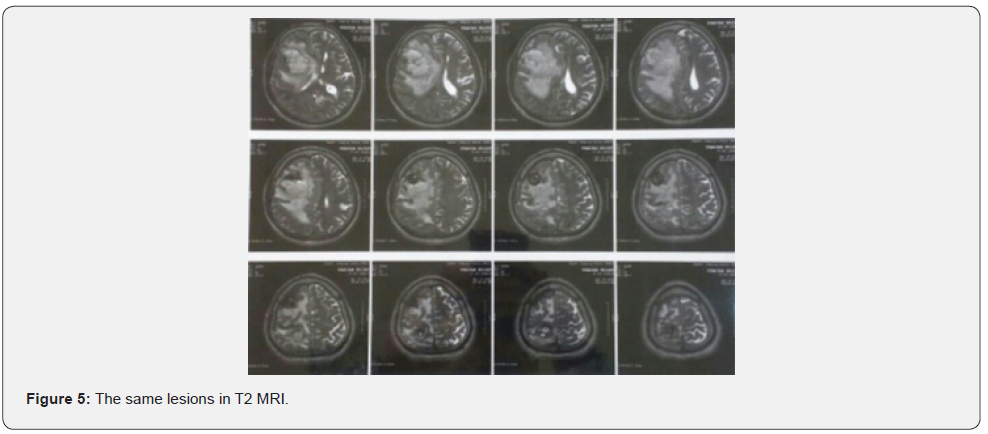

Both masses reported benign cardiac myxoma (Figure 3). No more work up was done for intra cranial lesions. New neurological deficits occurred 3 weeks before admission. Right hemi facial paresis, left hemi paresis (4/5), ataxia and several generalized tonic-clonic seizures developed. Other neurologic examinations were normal. In the Brain, CT scan space occupying lesions with low attenuation and severe edema was seen in the right parieto-occipital lobe which enlarged when compared to the images of the previous year. Two hyper signal lesions at the right parieto-occipital lobe with severe edema were seen in T1 and T2 and popcorn or burry view at GAD T1 MRI seen (Figures 4-6). In other surveys, including abdominal and pelvic ultrasonography, abdominal CT scan and fondus examination, there was no pathologic finding.